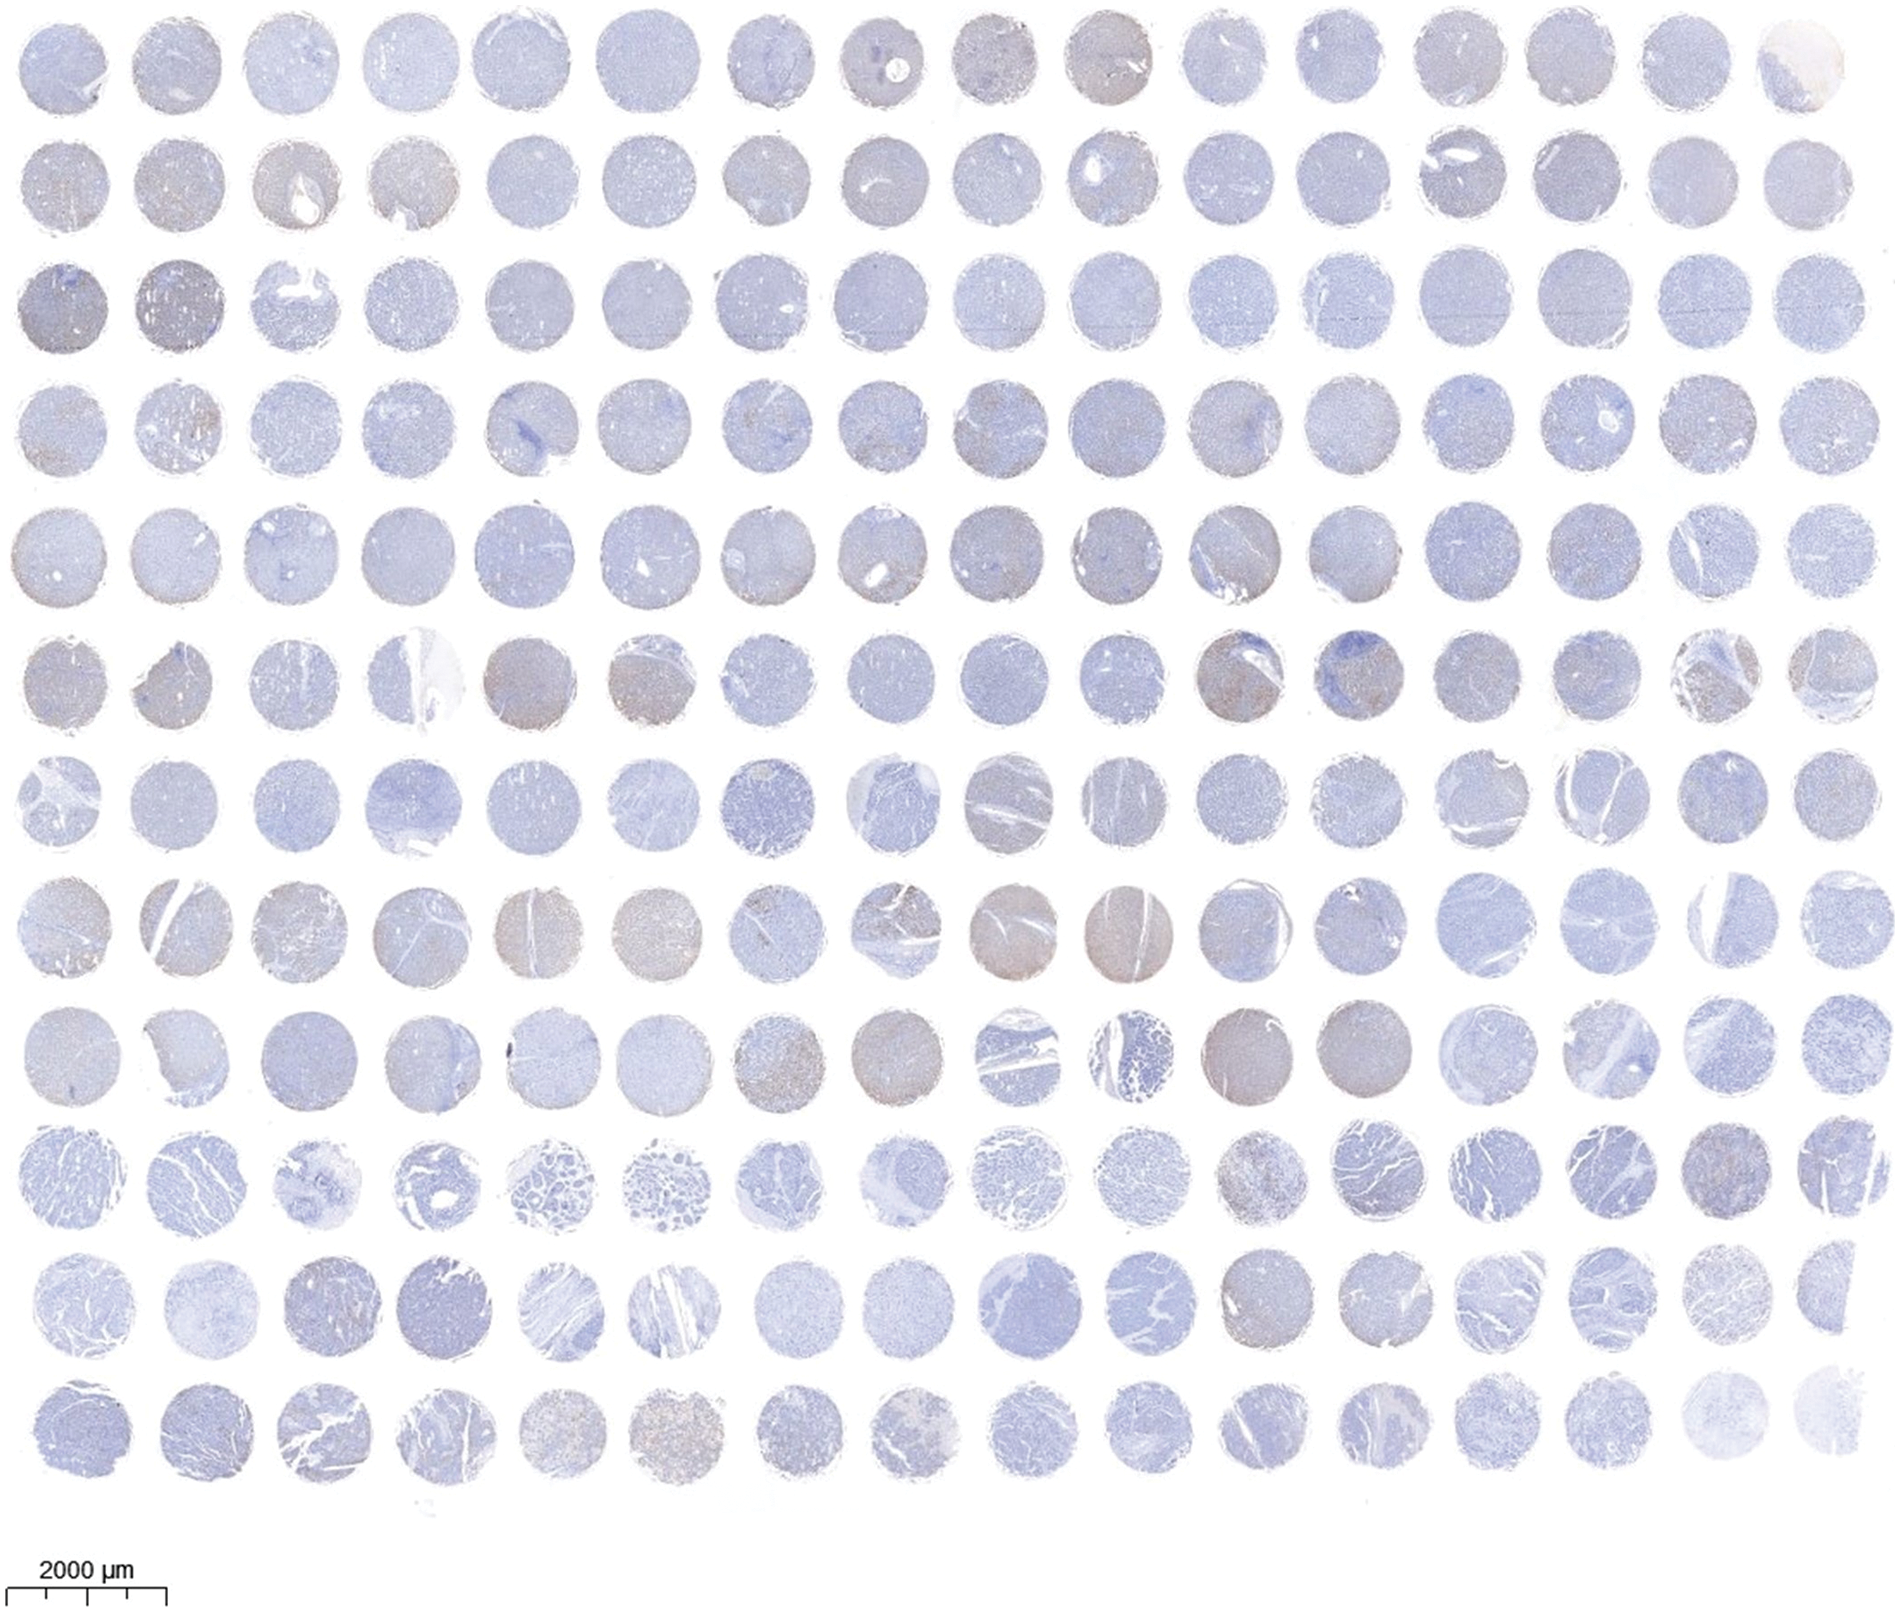

Tissue array and immunohistochemistry (IHC)

The human liver tissue array (DC-Liv00009) was obtained from Alenabio, Inc. (Xi’an, China) and analyzed according to the manufacturer’s instructions. In summary, the tissue sections of the human liver tissue array or the mice tumor tissues were deparaffinized and rehydrated and then endogenous tissue peroxides were quenched. The sections incubated with 3% H2O2 #88597 (Sigma, Billerica, MA, USA) for 10 min and then blocked with 1% BSA for 20 min. The sections were then incubated overnight at 4°C with corresponding primary antibodies (1:1000). Subsequently, the sections were incubated at 37°C for 1 h with HRP-labeled secondary antibodies (1:1000), and then were stained with DAB reagents #D8001 (Sigma, Billerica, MA, USA) and counterstained with hematoxylin. The tissues were examined and imaged with the microscope at 400× magnification. The IHC stains were assessed by figuring an H-score, and H-score greater than 6 indicates high EMP2 protein expression while H-score less than 6 indicates low EMP2 protein expression.

EMP2 promoted cellular autophagy and invasion in HCC cells

Immunohistochemical staining was performed to evaluate the expression level of EMP2 protein in liver disease tissue microarrays. HCC tissue exhibited a significantly higher positive rate of EMP2 compared to normal liver tissue. Furthermore, in HCC tissue, a higher level of EMP2 protein expression was associated with greater morphological heterogeneity and higher malignancy. The EMP2 positive stained ratio were around 20% in the normal liver and chronic hepatitis tissues, and over half of HCC tissue with high EMP2 staining (Figs. 4A and A1, Table A2). EMP2 was primarily localized in the cytoplasm, with minimal nuclear staining observed. The experimental results demonstrated an increasing trend in EMP2 protein expression as liver disease progressed from inflammation to liver cirrhosis and ultimately to HCC. Moreover, the expression level of EMP2 protein in HCC tissue positively correlated with the malignancy grade, indicating a significant role of EMP2 in the progression of liver diseases. To further validate these findings, six pairs of HCC tissues and matched adjacent normal liver tissues were collected. In five out of the six tissue samples, HCC tissues exhibited significantly higher levels of EMP2 expression compared to adjacent liver tissues. However, in one pair of tissues, the difference in EMP2 protein expression between HCC tissues and adjacent liver tissues was not sound (Figs. 4B–4D). In addition, the level of EMP2 protein expression was assessed in various liver or liver cancer cell lines. EMP2 protein expression was low in the normal liver epithelial cell line THLE-3. In contrast, the level of EMP2 protein expression was relatively high in five HCC cell lines (including Hep-3B, HepG2, SNU182, Huh-7, and SK-Hep-1).

Figure 4: The EMP2 protein expression levels in HCC tissues and cell lines. (A) The representative images of EMP2 IHC staining in HCC and adjacent normal liver tissues, scale bar = 100 μm. (B and C) The western blot of EMP2 in six paired HCC and adjacent normal liver tissues; *p < 0.05; **p < 0.01; ***p < 0.001. (D) The western blot of EMP2 in several HCC cell lines.

Figure A1: The images of EMP2 IHC staining in the tissue microarray of liver diseases and adjacent normal liver tissues.